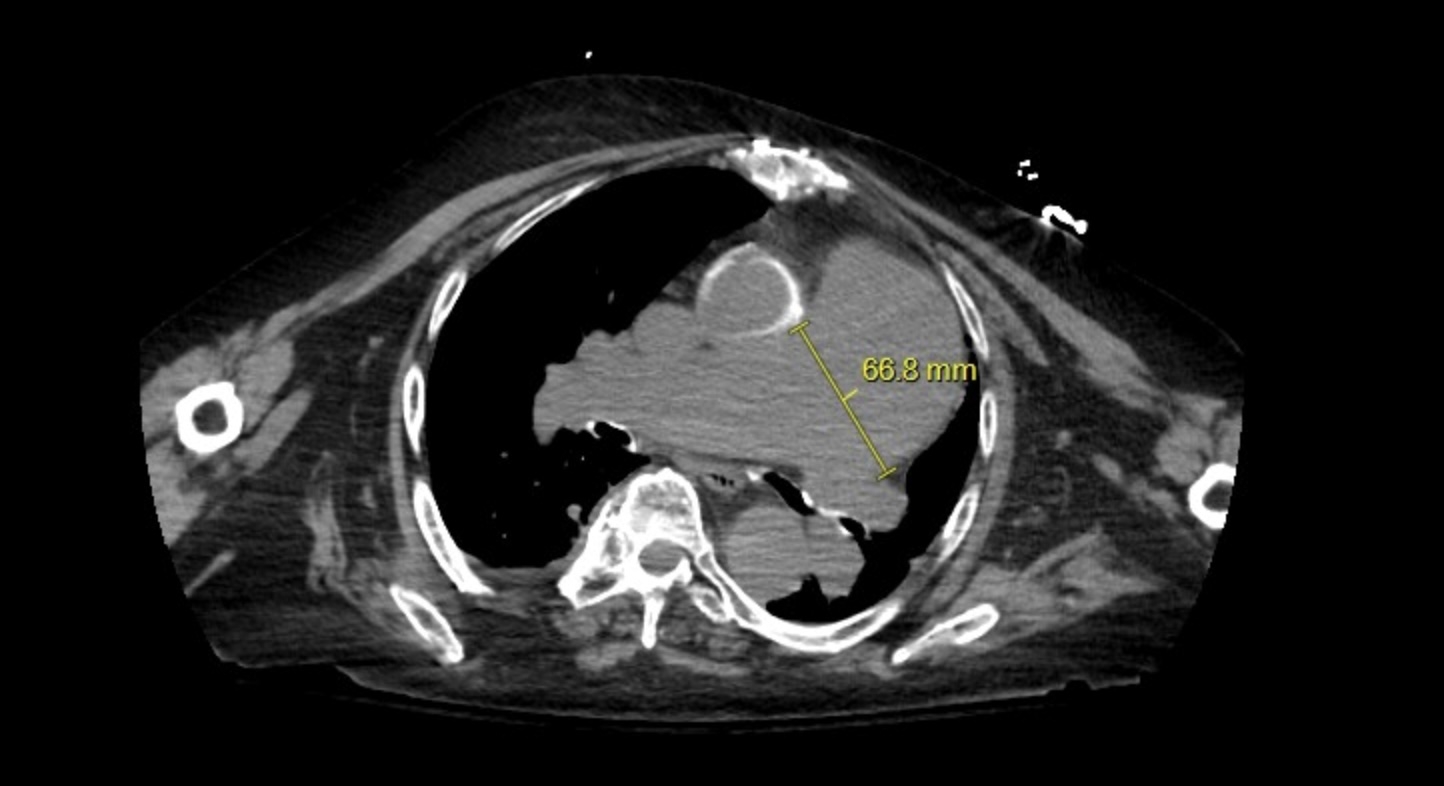

75-year-old woman with a PMH of hypertension, Group I pulmonary artery hypertension, HFpEF, non-obstructive CAD, aortic insufficiency s/p mechanical aortic valve replacement on warfarin since 02/2014, hyperlipidemia who was admitted due to altered mental status. Physical exam was remarkable for 4/6 diastolic murmur, 3/6 aortic murmur, prominent P2, and parasternal lift and no JVD or lower extremity edema. CXR incidentally showed enlarged pulmonary artery and CT chest showed PAA at 6.6 cm. Echocardiogram confirmed moderate to severe pulmonary hypertension and a markedly dilated PAA with pulmonary valvular insufficiency. In addition, she had an ascending aortic aneurysm with moderate aortic insufficiency. The two coinciding aneurysms could be distinct in etiology due to sequela of high pressure vessel wall degradation from pulmonary artery hypertension and systemic hypertension or related due to vasculitis or cystic medial necrosis/connective tissue disease. Due to multiple concomitant aneurysms, the patient is pending further workup.

Aneurysms are focal dilations with PAA larger than 29 mm and ascending aortic aneurysm larger than 44 mm. Common etiologies include vasculitis, connective tissue disease, and high vessel pressure. Due to the risk of fatal pulmonary hemorrhage, PAAs are critical. Diagnosis of PAA is via CTA and of aortic aneurysm is via TTE with annual monitoring. Surgical intervention is greater than 45-55 mm depending on risk factors for ascending aortic aneurysm and greater than 55 mm for PAA. Surgical interventions for PAAs include stent graft, aneurysmorrhaphy, lobectomy, aneurysmectomy, and pneumonectomy. Surgical resection comes with high risk in patients with severe pulmonary hypertension. Treating the underlying pulmonary artery hypertension is crucial to long term management along with determination and treatment of underlying cause.